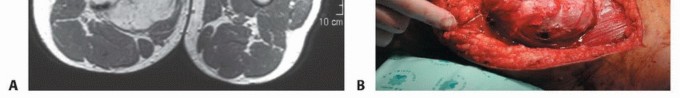

لطالما شكلت أورام الأنسجة الرخوة في الفخذ تحديًا كبيرًا للأطباء والمرضى على حد سواء، خاصة تلك التي تنمو في منطقة العضلات المقربة الحساسة. هذه المنطقة، التي تقع في الجزء الداخلي من الفخذ، هي ثاني أكثر المواقع شيوعًا لظهور هذه الأورام بعد الجزء الأمامي، وتتسم بقربها الشديد من الحزمة العصبية الوعائية الرئيسية (الشريان الفخذي، الوريد الفخذي، العصب الفخذي)، مما يجعل أي تدخل جراحي فيها محفوفًا بالمخاطر ويتطلب دقة متناهية وخبرة جراحية استثنائية.

في عقود مضت، كان التعامل مع الأورام الكبيرة أو المعقدة في هذه المنطقة غالبًا ما ينتهي بالبتر، مما كان يترك أثرًا نفسيًا ووظيفيًا عميقًا على حياة المريض. لكن بفضل التطورات المتسارعة في عالم الطب والجراحة، لم يعد البتر هو الخيار الوحيد. لقد شهدت التقنيات الجراحية تطورًا مذهلاً، مدعومة بتقدم هائل في التشخيص التصويري والعلاجات المساعدة مثل العلاج الكيميائي والإشعاعي، مما فتح آفاقًا جديدة أمام الحفاظ على الطرف المصاب. أصبح الهدف الأسمى هو استئصال الورم بالكامل مع الحفاظ على أكبر قدر ممكن من وظيفة الطرف، مع تقليل معدلات تكرار الورم وتحسين جودة حياة المريض بشكل جذري.

- التشخيص: يتطلب فحصًا شاملاً، تصويرًا متقدمًا (MRI، CT)، وخزعة نسيجية لتأكيد التشخيص وتحديد نوع ودرجة الورم.

- العلاج: يتضمن عادةً الجراحة (الاستئصال الواسع مع الحفاظ على الطرف)، وغالبًا ما يتبعها علاج إشعاعي أو كيميائي لتقليل خطر التكرار أو انتشار الورم.